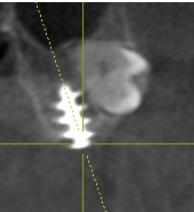

I recently placed an implant that I’m worried about the prognosis. My previous cases have all been free handed. I had my lab make a guide for this case. I ended up relying too much on the guide and placed the implant too close to the adjacent tooth (0.8mm). Has anyone else placed one this close and had it fail or be successfull? Im wondering what my next steps should be? I informed the patient it was closer than I would have liked, have her planned back for a follow up in 2 weeks and plan to leave it buried for 4 months.

Here’s the pic that @nguyenanhduytrung was posting. He said it’s been in 10 years and no issues @jmsdds

IMG_7001